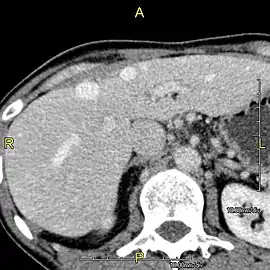

Left lobe liver tumor

The liver is a vital organ and supports almost every other organ in the body. Because of its strategic location and multidimensional functions, the liver is prone to many diseases.[51] The bare area of the liver is a site that is vulnerable to the passing of infection from the abdominal cavity to the thoracic cavity. Liver diseases may be diagnosed by liver function tests–blood tests that can identify various markers. For example, acute-phase reactants are produced by the liver in response to injury or inflammation.